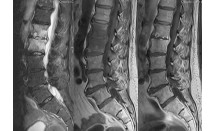

La chondromatose synoviale est une métaplasie du tissu synovial caractérisée par la formation de corps cartilagineux (chondromes) ou ostéo-cartilagineux (ostéochondromes) dans les articulations, les bourses séreuses ou les gaines synoviales. Il s'agit d'une affection rare, mono-articulaire, dont on distingue une forme primitive et une forme secondaire (arthrose, traumatisme, ostéochondrites, ostéonécroses aseptiques, arthrite...). L'étiologie et la pathogénie de la forme primitive sont inconnues.